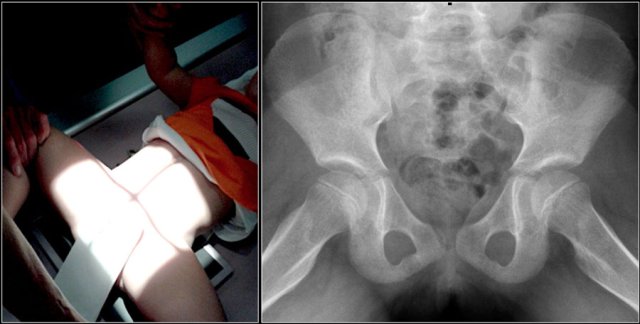

In most cases osseous pathology can be excluded with a frog-leg lateral (or Lauenstein) view only.

In case of suspected pathology on the frog-leg lateral view, an additional AP radiograph should also be acquired for orthopedic and follow-up purposes.

Children with cerebral palsy are at an increased risk for hip dislocation, and in these cases an AP-view is recommended. An AP-view is also recommended in other situations an adequate frog-leg lateral view is not possible.

Lead Shielding

The reduction of gonadal radiation exposure with lead shielding is negligible.

Gonadal shielding is dissuaded for the following reasons:

- risk of masking important diagnostic information

- a higher number of retakes

- possible shielding of automatic exposure control chambers.

Note: as this is a relatively new insight, some of the images in this article do still include lead shielding.